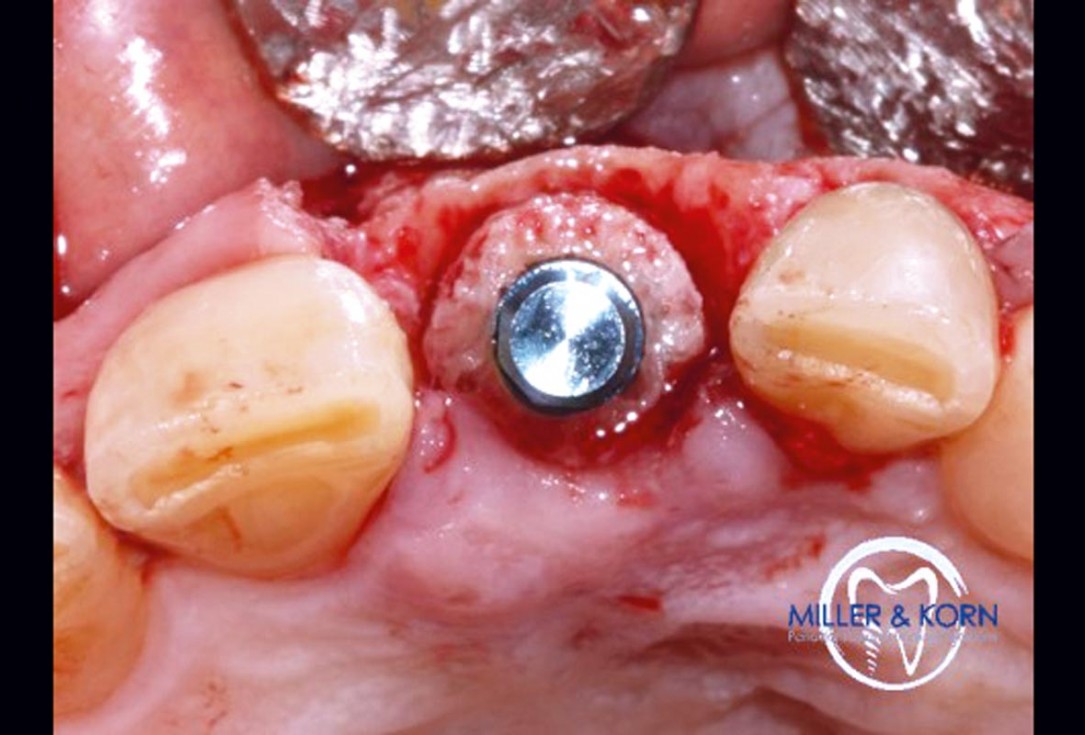

19/39 - Immediate implant insertion through the bone ringImmediate implant placement and correction of horizontal and vertical bone loss using an allograft bone ring, cerabone® and Jason® membrane - Drs. Miller and Korn

-